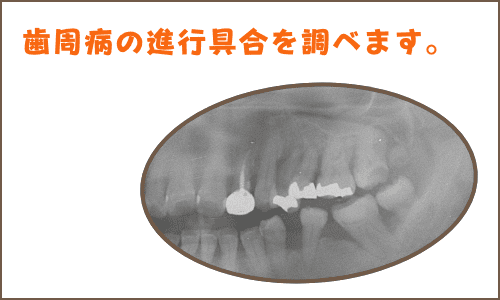

歯周病の程度を知るためには、骨の吸収がどの程度進んでいるのか知る必要があります。おおまかに知るにはレントゲン撮影でもわかるのですが、さらに詳細に歯の周りの骨のどの部分がどの程度の吸収が進んでいるのか調べることで、咬合との関係や、歯ブラシで特に注意すべきことが分かります。